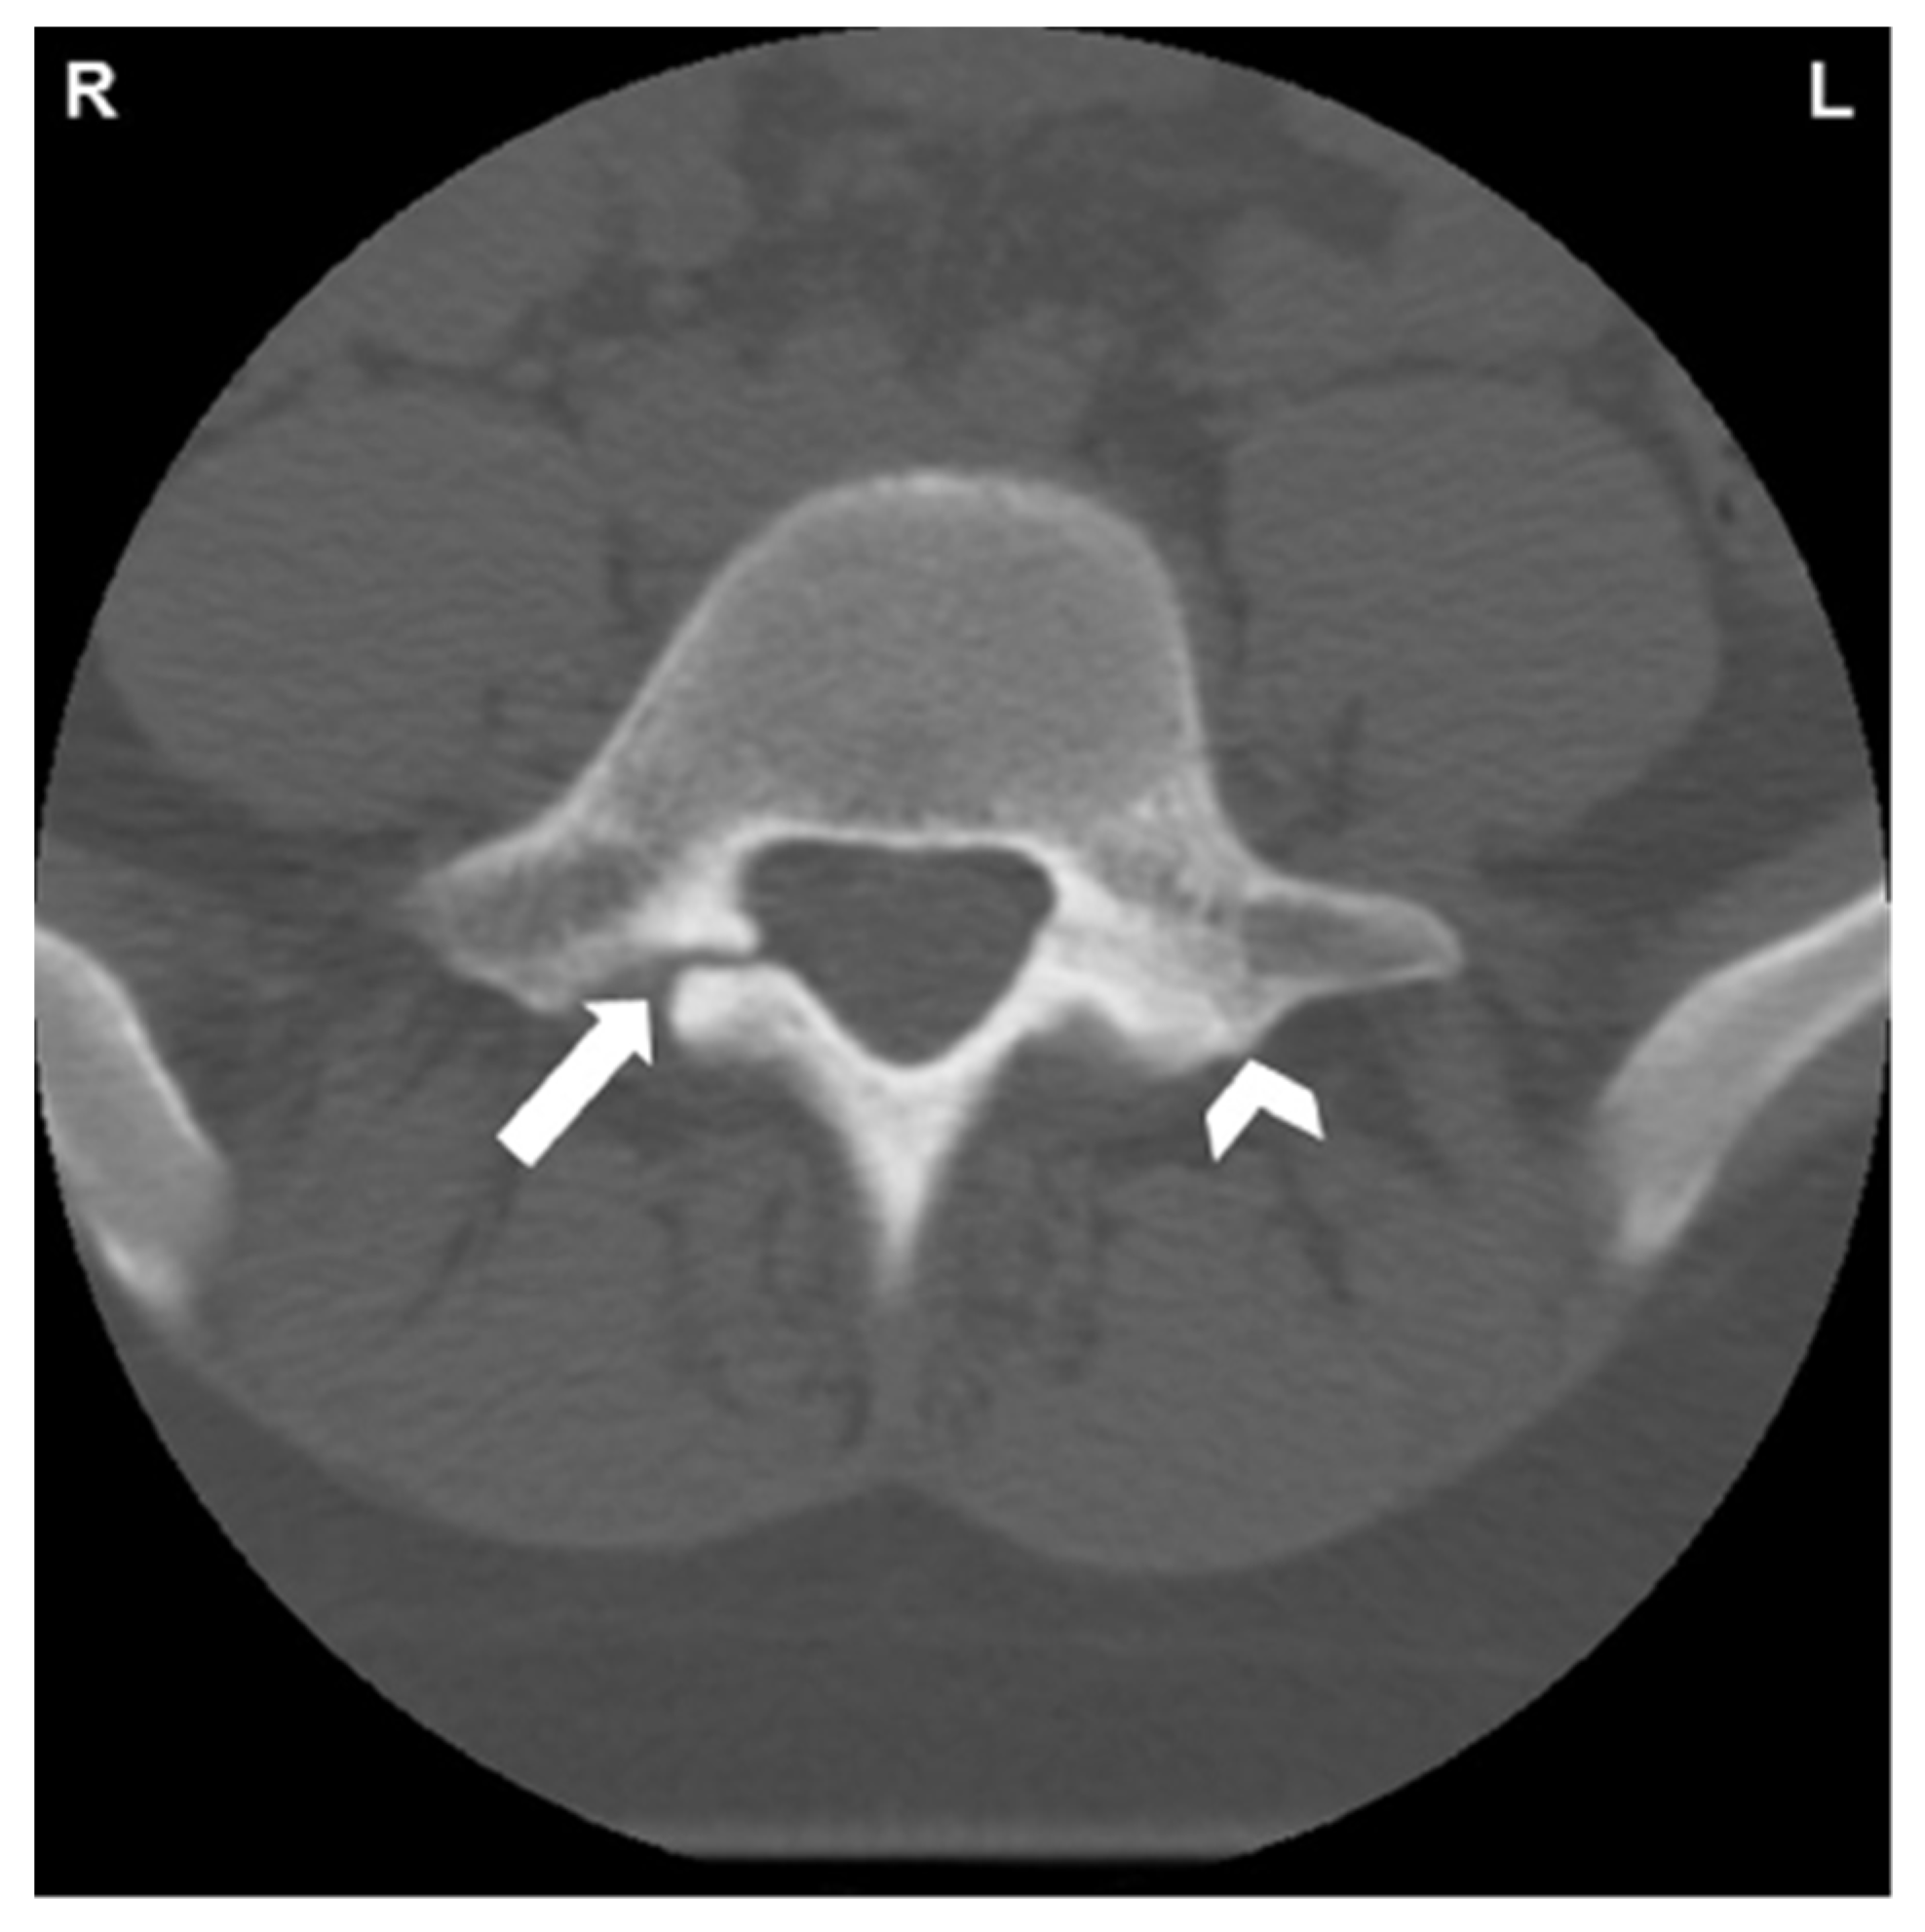

- Fayed, I.; Conte, A.G.; Voyadzis, J.-M. Success and failure of percutaneous minimally invasive direct pars repair: Analysis of fracture morphology. World Neurosurg. 2019, 126, 181–188. [Google Scholar] [CrossRef]